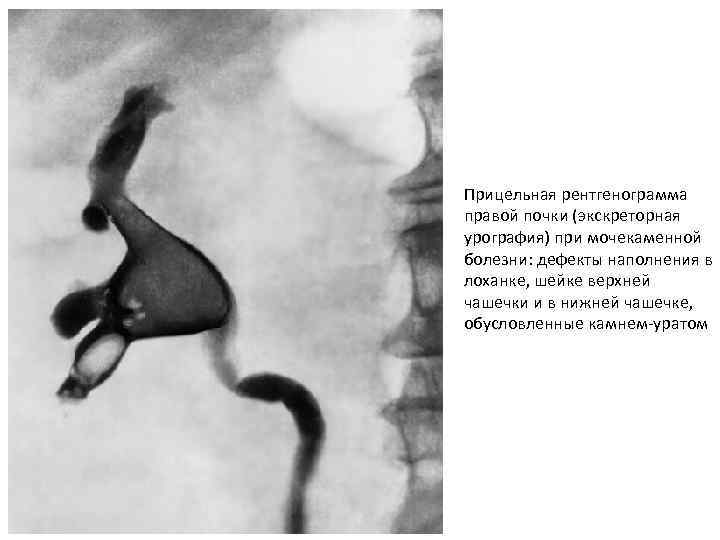

Прицельная рентгенограмма правой почки (экскреторная урография) при мочекаменной болезни: дефекты наполнения в лоханке, шейке верхней чашечки и в нижней чашечке, обусловленные камнем-уратом